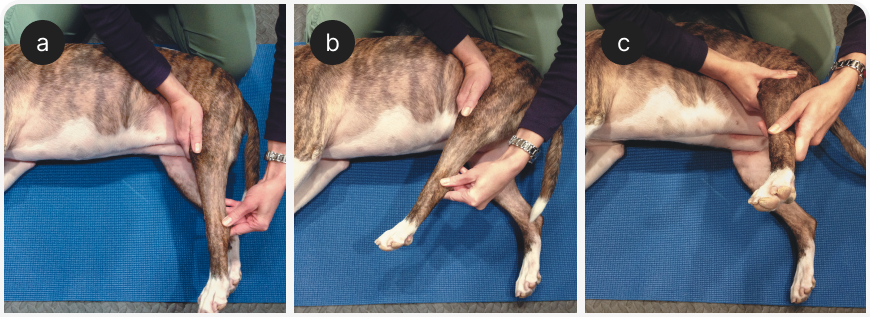

Основное преимущество повышения эластичности мышц – снижение риска микротравм. Регулярные занятия по растяжке подколенного сухожилия могут быть полезны для пород, предрасположенных к фиброзной миопатии (Рисунок 8). Наибольших успехов удается добиться, когда стретчингом занимаются на регулярной основе. В идеале такие тренировки следует проводить, когда мышцы уже разогреты и становятся более податливыми и растяжимыми. Собакам-спортсменам рекомендуются растяжки мышц, которые отвечают за резкие всплески усилий. Эти занятия следует проводить через день.